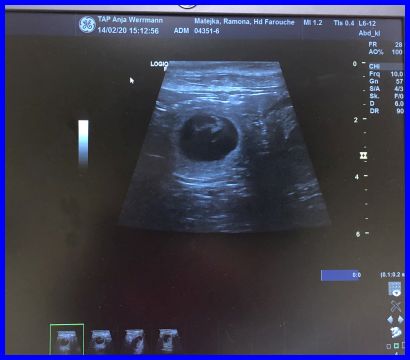

Da ist es, das erste Baby, man kann es ganz deutlich in der Fruchtblase sehen.

Theoretisch könnten das vier Babys sein...